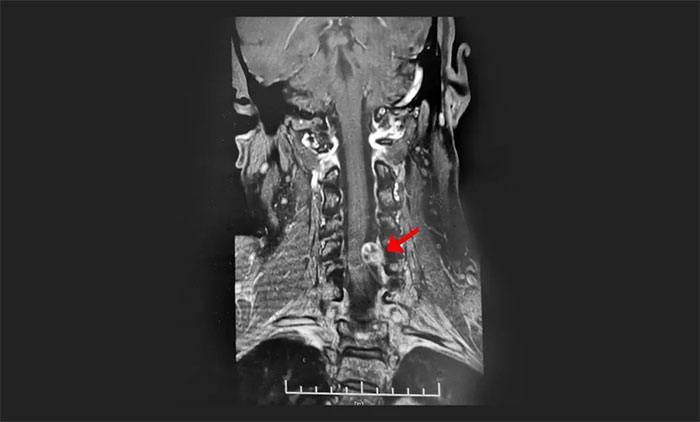

脊髓腫瘤(Tumor of Spinal Cord)亦稱椎管內(nèi)腫瘤,是指生長于脊髓及與脊髓相近的組織,包括神經(jīng)根、硬脊膜、血管、脊髓及脂肪組織等的原發(fā)、繼發(fā)腫瘤?煞譃榧顾鑳(nèi)及脊髓外腫瘤。原發(fā)脊髓腫瘤每年新發(fā)病例2.5/10萬,大約是腦腫瘤發(fā)病率的1/10。在組織發(fā)生學(xué)上...[詳細(xì)]

發(fā)生于頸椎部位的椎管內(nèi)腫瘤,往往可表現(xiàn)出類似頸椎病的癥狀。神經(jīng)外科于耀宇主任提醒,日常生活中,如果出現(xiàn)長時(shí)間的頸背疼痛、肢體麻木乏力、感覺減退、行走不穩(wěn)等癥狀,要留意椎管內(nèi)腫瘤的可能,及時(shí)到具備專科診治能力的醫(yī)院明確診斷。...[詳細(xì)]

由于椎管內(nèi)腫瘤初始癥狀與頸椎病類似,表現(xiàn)為肢體麻木、疼痛等,容易與頸椎退化性疾病混淆,導(dǎo)致延誤治療。盧云鶴博士提醒:對(duì)于反復(fù)腰腿痛、頸肩痛,要有高度的警惕性,尤其是疼痛超過兩周且疼痛不易緩解的患者,應(yīng)盡快到醫(yī)院就診,明確診斷,及時(shí)治療。...[詳細(xì)]